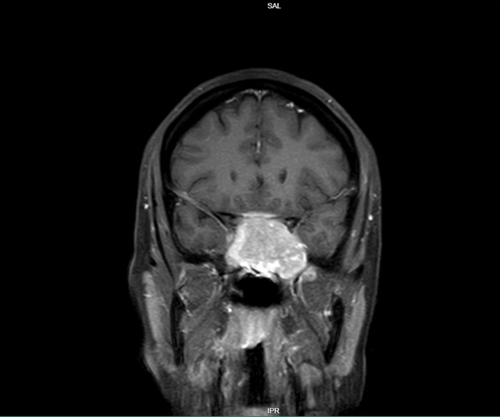

We report the case of a 45-year-old woman who presented with complaints of vision changes and dryness in her eye. Magnetic resonance imaging (MRI) revealed a large, homogeneously contrast-enhancing mass located in the sphenoid sinus, accompanied by evidence of bone remodeling at the skull base (Figure 1,2).

Figure 2: T1 MRI coronal view of the lesion

Figure 1